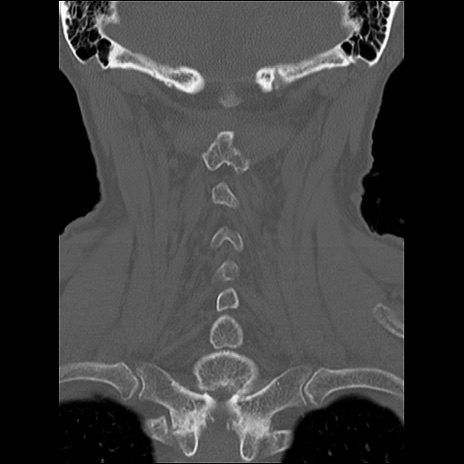

頚椎CT

矢状断像